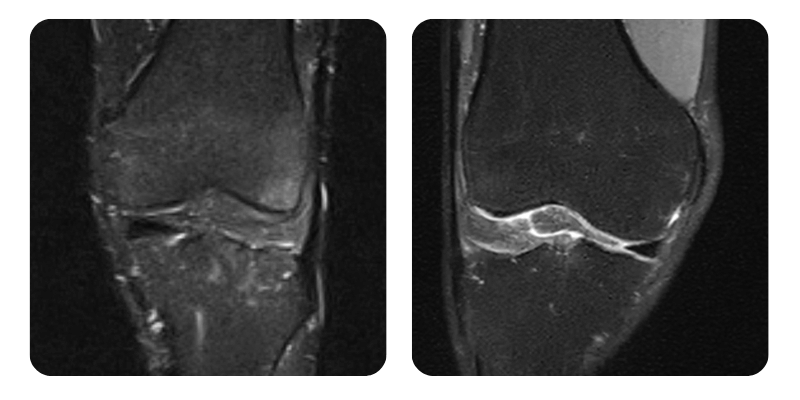

Prima

Dopo

R.A., 37 anni - Osteonecrosi del condilo mediale del femore sinistro

Risultato: Alla valutazione il paziente si presenta senza dolore. Gli esami di imaging mostrano una remissione dell'edema del 90%, con mobilita normale. Il paziente ha seguito, di propria iniziativa, altre 20 sedute. Alla rivalutazione lo stato generale e rimasto buono, senza ulteriori sintomi, e gli esami di imaging mostrano remissione completa.